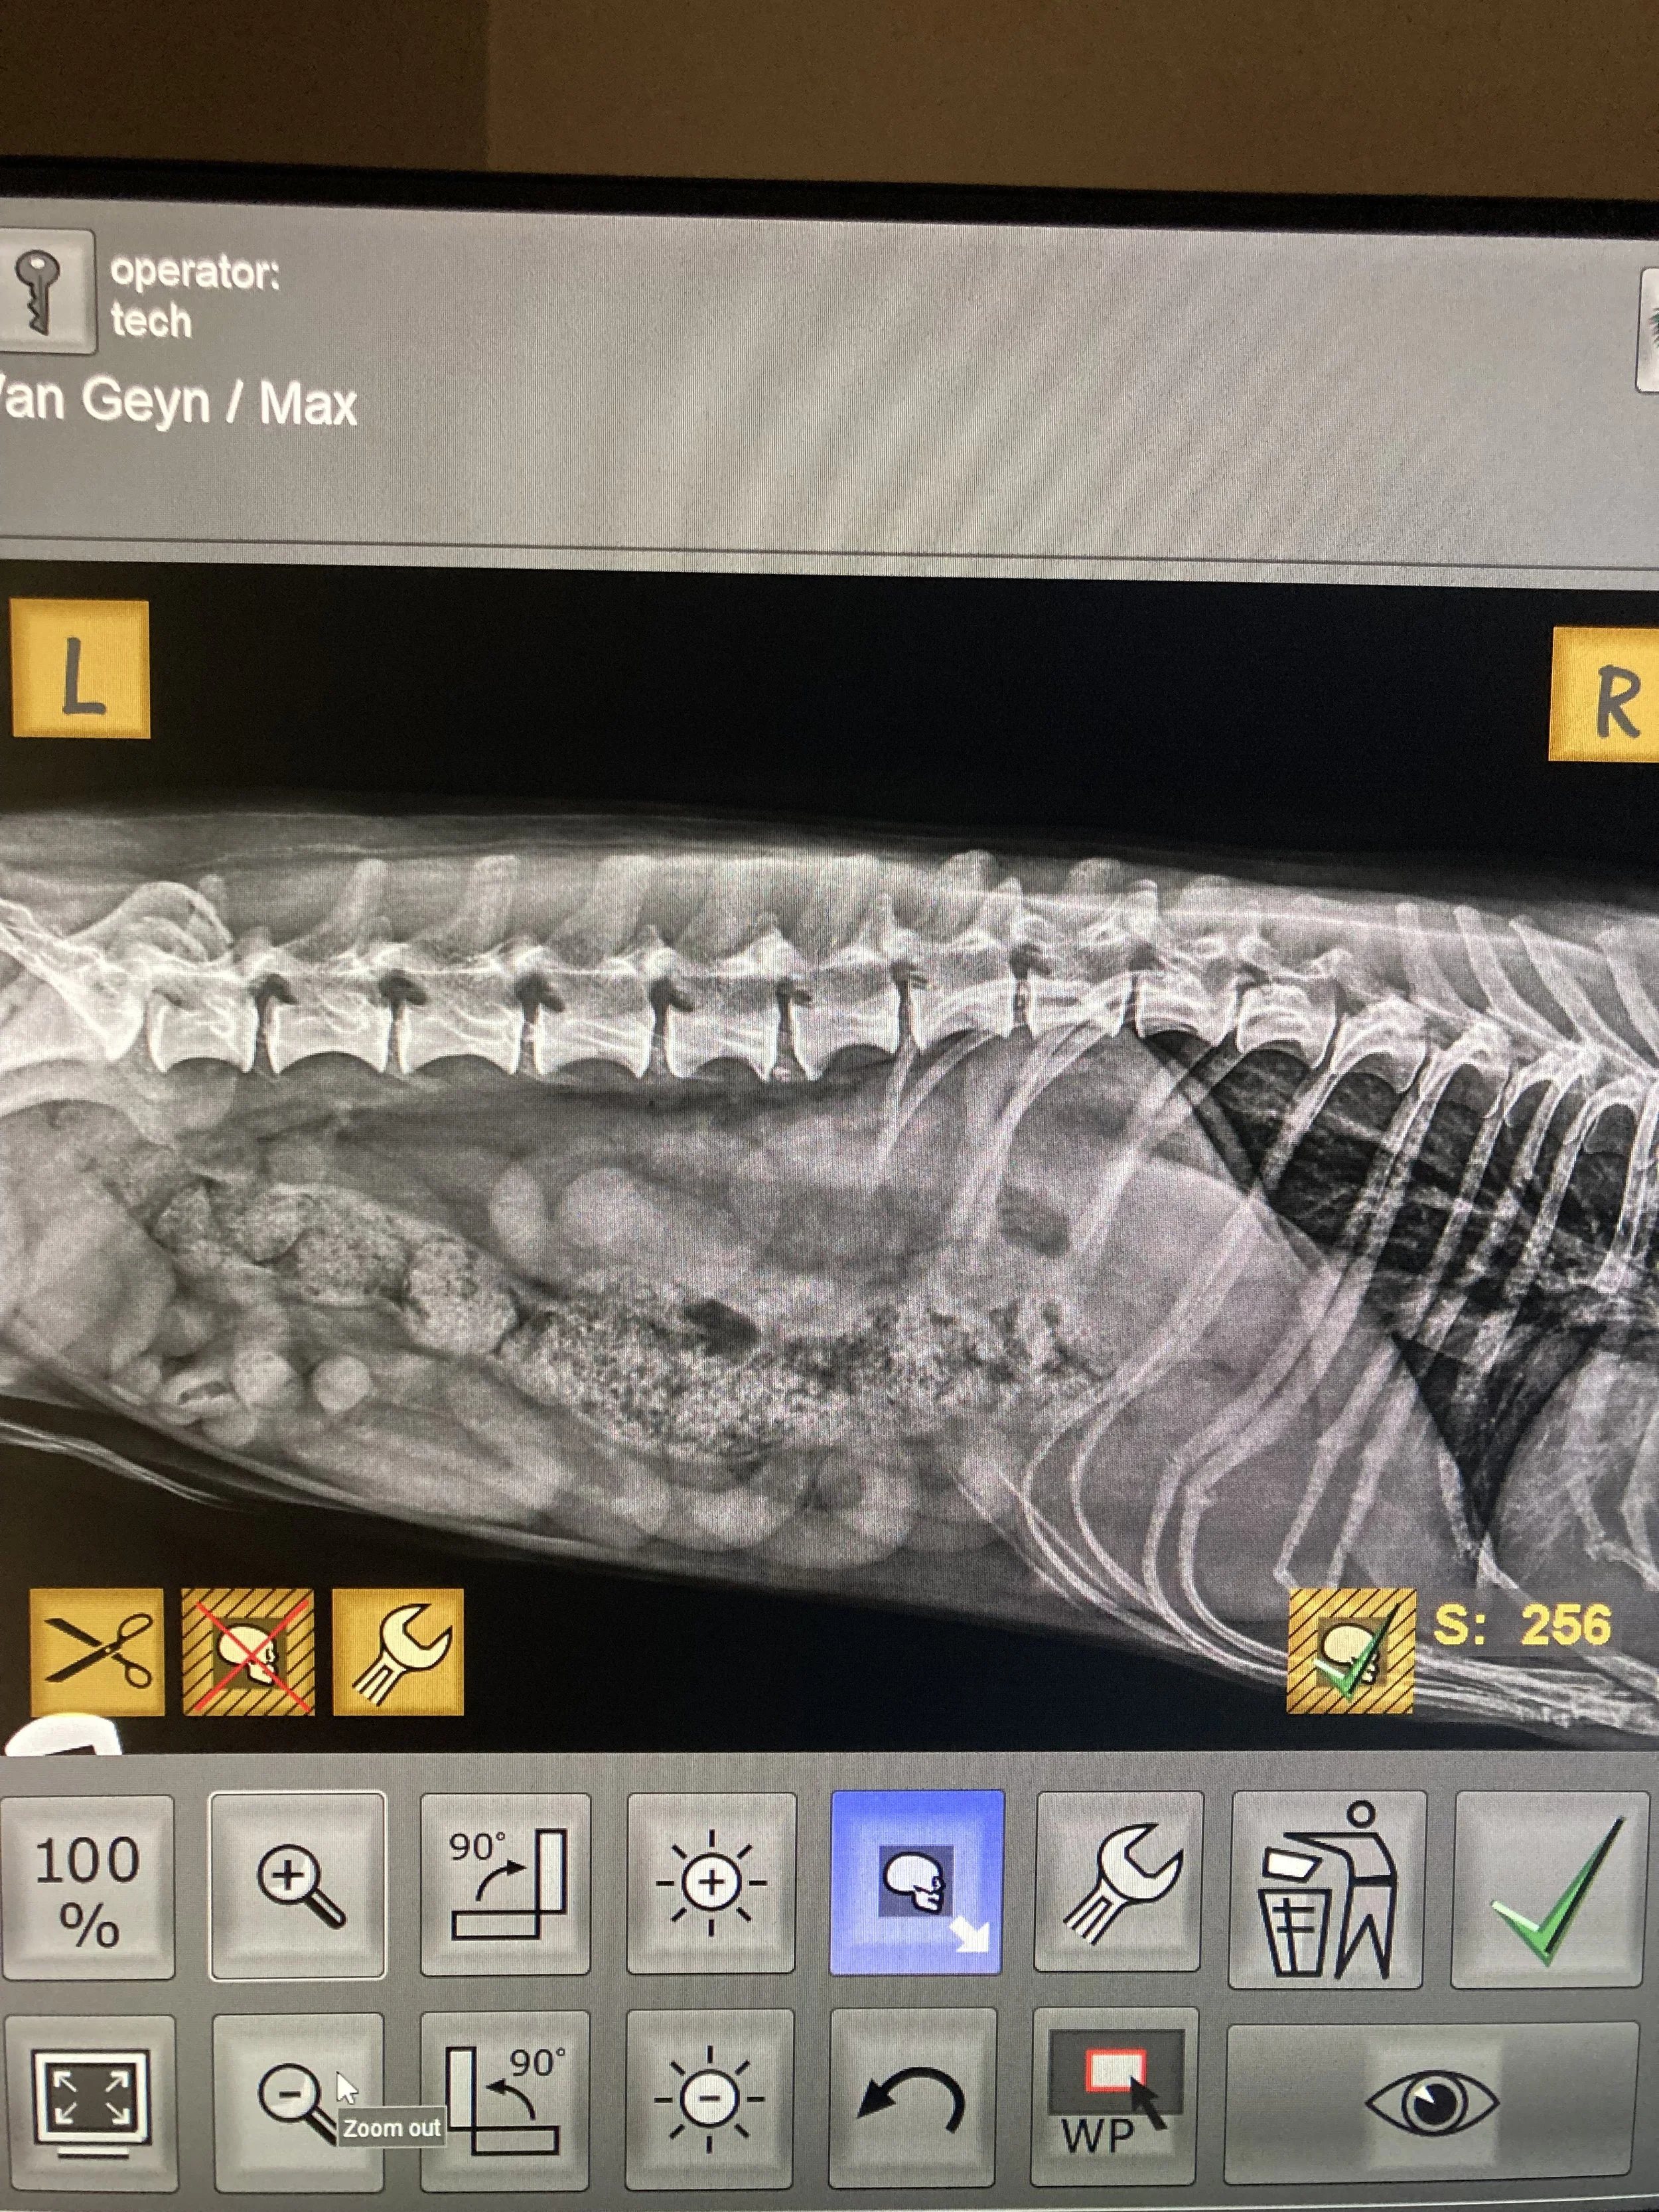

At Silvercreek Animal Hospital, we use digital radiography (X-rays) to help diagnose a wide range of health conditions quickly and safely. X-rays give us a detailed view of your pet’s bones, joints, and internal organs—allowing us to detect issues that can’t be seen during a physical exam alone.

- Tumors or abnormal growths

- Bladder stones